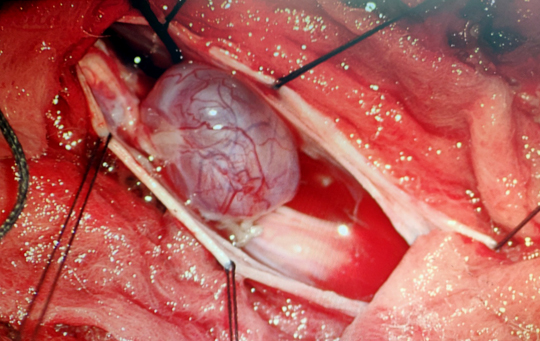

Operation Theatre